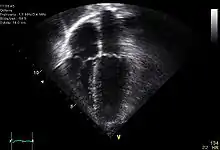

Le cœur est un organe intra thoracique, entouré d'air (les poumons) et d'os (les côtes). Ces deux dernières structures ne laissent pas transmettre les ultrasons, rendant l'examen plus complexe. On se sert ainsi d'un nombre limité de « fenêtres » anatomiques, lieux où le cœur peut être visualisé par l'échocardiographie, sans interposition aérienne ou osseuse.

- Le cœur est un organe tridimensionnel battant. L'échocardiographie effectue des coupes de cet organe et les résultats peuvent varier suivant le plan de coupe choisi. L'examen reste dépendant de l'expérience de l'examinateur.